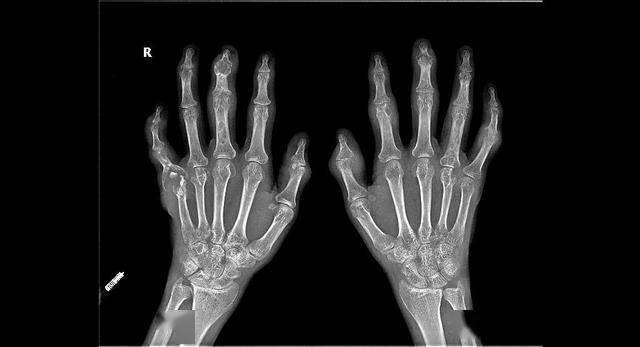

如何确定是痛风石?这五招鉴定法痛风专家周桂兰告诉你!

老人76岁,他手指#痛风石 并不是很大,但片子显示手指上痛 - 抖音

看了这双长满痛风石的手,你还不在乎尿酸高吗?